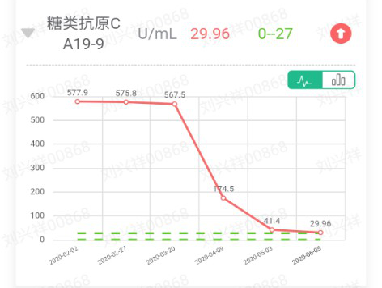

糖类抗原CA19-9,577.9U/mL↑

2020-02-27 肿瘤标志物:癌胚抗原,349.40ng/mL↑;甲胎蛋白,1.66ng/ml;糖类抗原CA19-9,575.8U/mL↑;糖类抗原CA72-4,16.77U/ml↑;糖类抗原CA24-2,>200U/mL↑。

2020-03-20 肿瘤标志物:癌胚抗原,529.30ng/mL↑,甲胎蛋白,1.41ng/ml,糖类抗原CA19-9,567.5U/mL↑,糖类抗原CA72-4,42.43U/ml↑,糖类抗原CA24-2,>200U/mL↑。

2020-04-09 肿瘤标志物:癌胚抗原,213.70ng/mL↑,甲胎蛋白,2.18ng/ml,糖类抗原CA19-9,174.5U/mL↑,糖类抗原CA72-4,24.41U/ml↑,糖类抗原CA24-2,176.5U/mL↑。

2020-05-03 肿瘤标志物:癌胚抗原,61.77ng/mL↑,甲胎蛋白,1.63ng/ml,糖类抗原CA19-9,41.40U/mL↑,糖类抗原CA72-4,8.35U/ml↑,糖类抗原CA24-2,40.4U/mL↑。

2020-06-05 肿瘤标志物:癌胚抗原,27.40ng/mL↑,甲胎蛋白,2.15ng/ml,糖类抗原CA19-9,29.96U/mL↑,糖类抗原CA72-4,4.66U/ml,糖类抗原CA24-2,17.54U/mL。

主要肿瘤标志物变化情况。

该患者经西妥昔单抗联合化疗治疗后,患者临床症状好转。肿瘤标志物如:CEA、CA19-9、CA72-4、CA24-2均逐步下降中。影像学检查提示肝脏转移病灶较前缩小,未出现新的转移病灶。考虑治疗有效。